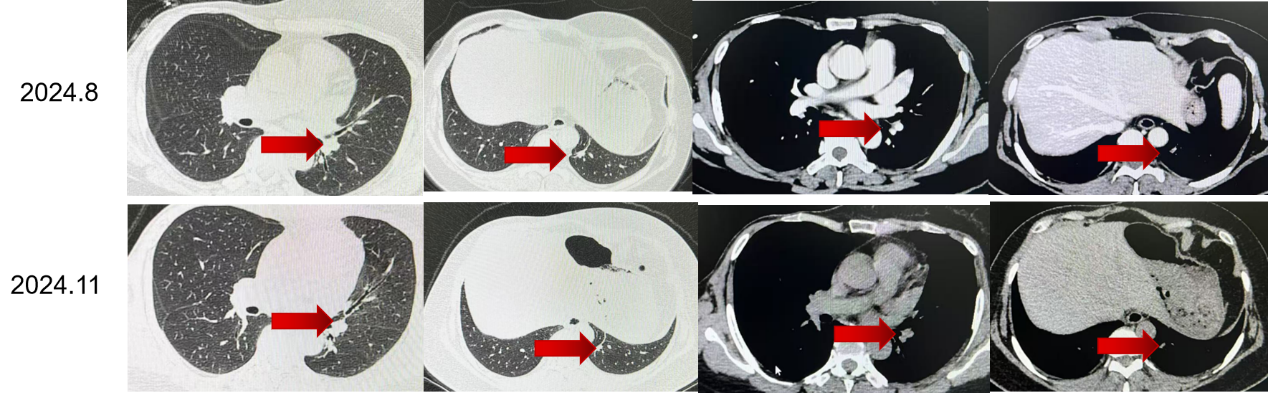

更换治疗方案:2024年6月,患者改用达尔西利150 mg,口服3周停1周,联合阿那曲唑1 mg qd治疗。

换用达尔西利联合阿那曲唑后,患者后续多次复查均提示病灶进一步缩小,2024年8月、2024年11月、2025年4月及2025年9月疗效评价均为PR。靶病灶总和由55 mm降至20 mm,整体缩小约63.6%,提示调整方案后患者获得了持续且稳定的影像学缓解。

从病程时间轴来看,患者术后至复发的DFS为14年8个月;初始一线治疗阶段获得了早期疾病控制,而在后续调整为达尔西利联合阿那曲唑后,至今持续获益中。对于需要兼顾疗效与治疗连续性的HR+/HER2-晚期乳腺癌患者而言,这一结果提示,在后续治疗策略优化后,患者仍有机会持续从CDK4/6抑制剂联合内分泌治疗路径中获益。